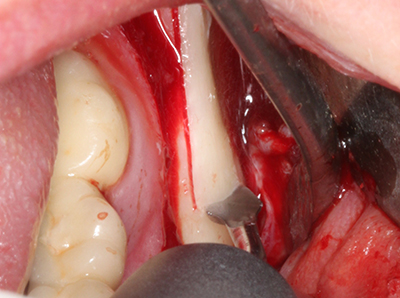

Il tessuto osseo non è semplicemente una struttura minerale, ma contiene anche una percentuale significativa di fibre di collagene. Ciò significa che non possiede solo una buona forza di compressione, ma anche un certo livello di flessibilità che è possibile sfruttare durante l'esecuzione degli accrescimenti di osso. Nella procedura di espansione classica con incisione ossea, la cresta alveolare atrofizzata viene incisa longitudinalmente ed espansa con cautela dopo aver raggiunto una profondità di osteotomia adeguata (figg. 13-16), idealmente senza una sostanziale rimozione del periostio (Brugnami, Caiazzo et al. 2014, Stricker, Fleiner et al. 2014). I sistemi a piastra e vite con distanza di espansione incrementale si sono dimostrati efficaci nella separazione delle due lamelle ossee restando al di sotto della soglia di frattura. In generale, sono richieste larghezze dell'osso residuo di almeno 3-4 mm (Chiapasco, Zaniboni et al. 2006) per garantire un'adeguata flessibilità e una copertura sufficiente dell'osso per gli impianti futuri. Se necessario, un'osteotomia di rilascio verticale su uno o più lati può migliorare la flessibilità. Una combinazione con ulteriori tecniche di accrescimento, in particolare dal lato buccale, è stata descritta come un'alternativa alla tecnica classica.

La procedura di incisione è particolarmente atraumatica e non comporta una perdita significativa di dimensione durante l'utilizzo delle seghe piezoelettriche, così come non si notano differenze rilevanti tra impianti in mandibole incise e impianti in una cresta alveolare senza deficit osseo (Chiapasco, Zaniboni et al. 2006, Danza, Guidi et al. 2009). Una sufficiente irrigazione continua è essenziale, tuttavia, in particolare con incisione profonda e localmente ristretta, per prevenire la sollecitazione termica nelle regioni apicali dell'osteotomia.